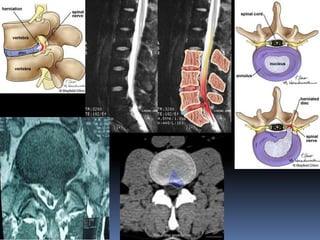

 Between the dura mater and periosteum of

the vertebrae is the epidural space that

contains many blood vessels and fat.

 Space between dura mater and archnoid-

subdural space-no CSF.

 Space between arachnoid and pia mater-

subarchnoid space-CSF, blood vessels, spinal

roots.